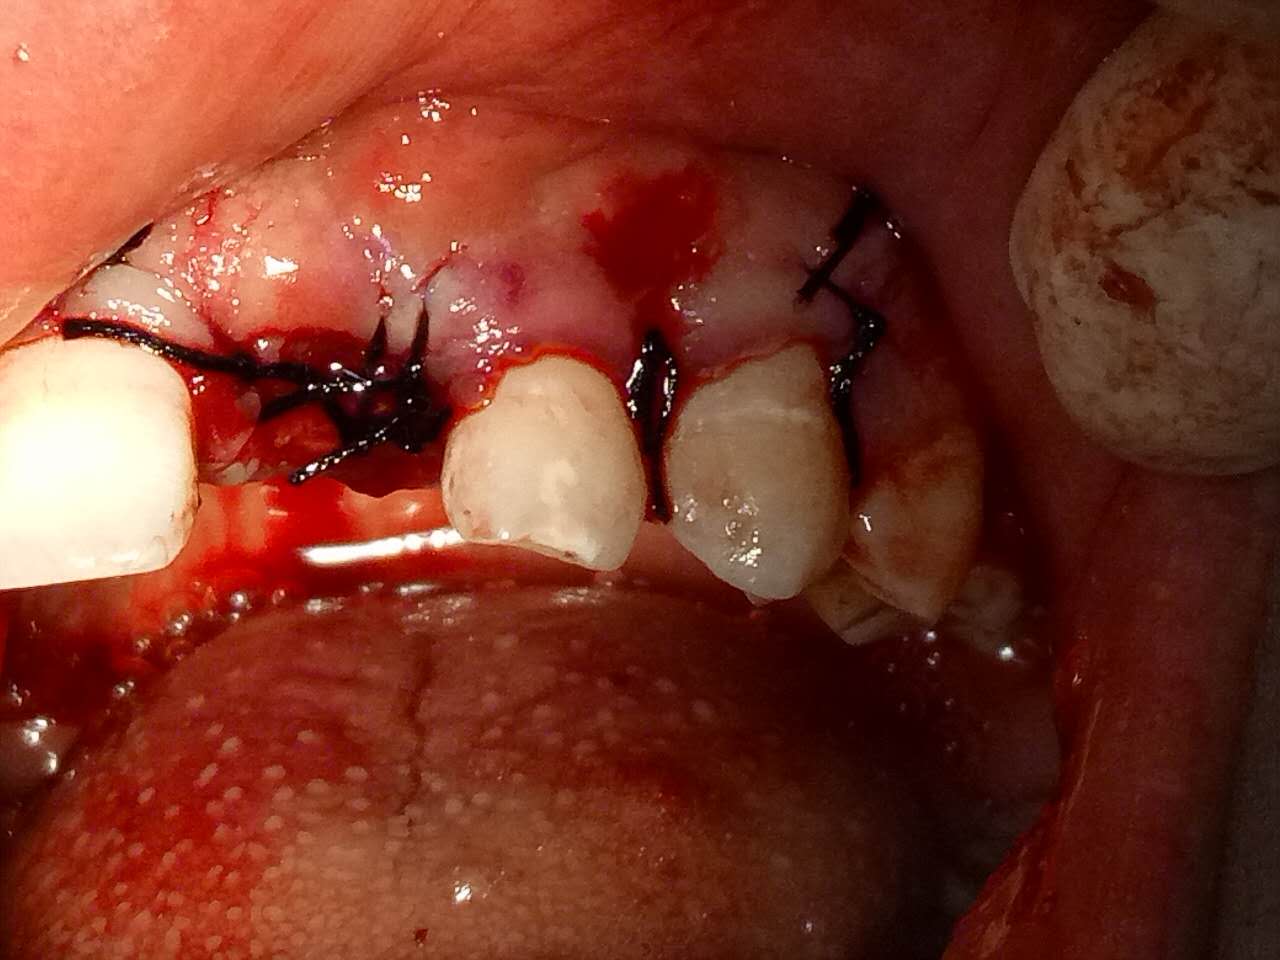

死髓牙2度,沒保留價(jià)值了,外傷造成的外吸收,即使到充也容易出問題。和患者溝通,要求做種植,用了兩個(gè)骨膠原,側(cè)切、尖牙沒事,側(cè)切做了一次根充

圖片來源于江思玉病例討論2群